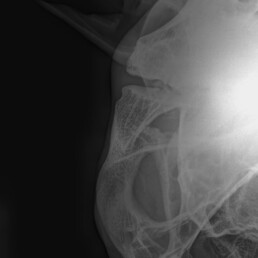

Weiterführende Untersuchungen: Röntgen

- makroskopische Umfangsvermehrung am linken Kiefergelenk

- röntgenologische Untersuchung beider Kiefergelenke zum Seitenvergleich

- beidseitige Befunde

Diagnose: beidseitige Kiefergelenksarthrose